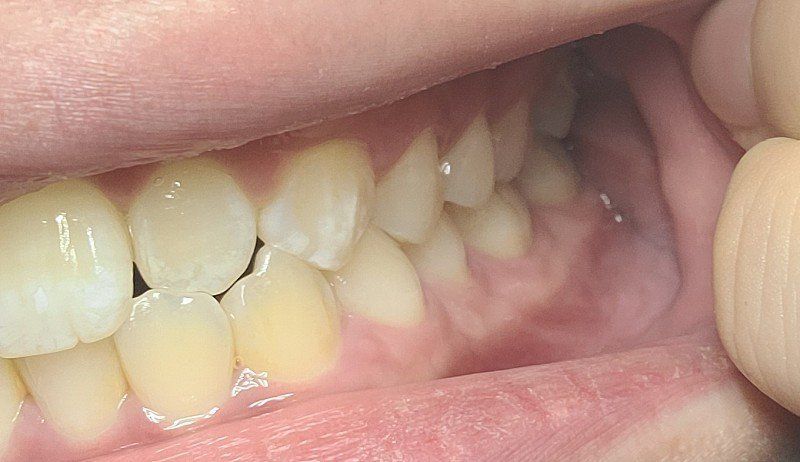

□앞니쪽 옆 치아 위아래가 하나씩 부딪히기는한데 이 치아때문에 앞니 두개가 벌어지는데 영향을 미치나요?

측절치는 사진과같이 아래치아와 바로 닿는것은 좋지 않습니다. 보통은 위의 치아가 아래치아를 조금 덮는식으로 교합되는것이 좋습니다. 장기적으로 볼때 좋진 않습니다.